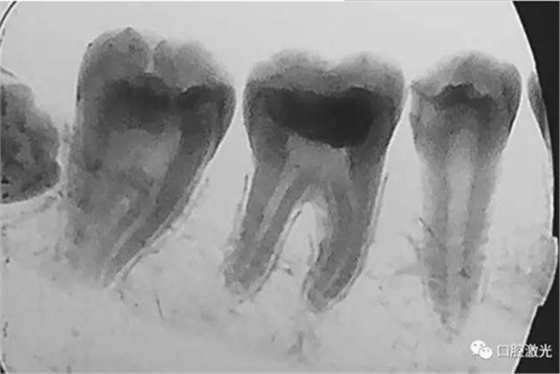

活髓理療治療結果令人滿意,沒有出血,也沒有出現(xiàn)碳化。患者沒有感受到不適并表示滿意。為了跟蹤激光輔助活髓切除術的治療效果,手術完成即刻和5周后分別拍攝了X光圖像。5周后的牙髓活性溫度測試也顯示陽性。

治療后5周